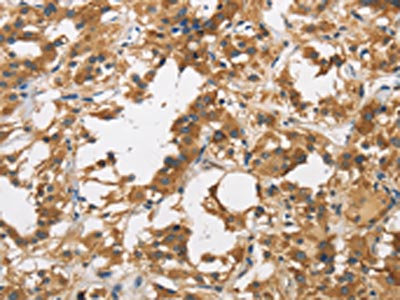

The image on the left is immunohistochemistry of paraffin-embedded Human liver cancer tissue using CSB-PA571416(DUSP23 Antibody) at dilution 1/30, on the right is treated with fusion protein. (Original magnification: ×200)

The image on the left is immunohistochemistry of paraffin-embedded Human thyroid cancer tissue using CSB-PA571416(DUSP23 Antibody) at dilution 1/30, on the right is treated with fusion protein. (Original magnification: ×200)